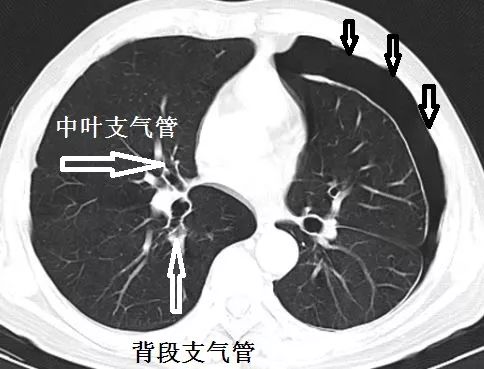

胸膜分为贴在胸壁的壁层胸膜和贴在肺表面的脏层胸膜。

仔细看看,这个患者的脏层胸膜增厚,提示气胸很可能不是近期的事情,很可能是长时间造成的,正常的肺表面不会有增厚的、白色的一圈。

追问病史,患者诉没有任何呼吸系统症状,气胸是偶然发现的。很明显,这个患者要考虑慢性气胸。

下面怎么办?慢性气胸很可能是非流动性气胸:气胸可能不随着体位大幅度变化。那么,在穿刺之前,做一个站立位胸片就显得很有必要。